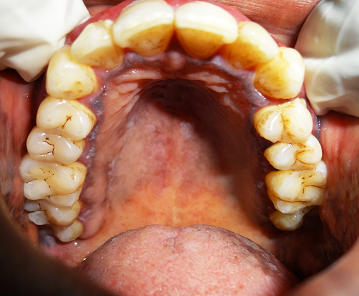

ORA PRECANCER

Oral precancers are usually asymptomatic and painless so the patient is unaware of the lesions presence.

aphthous ulcers

desquamative gingivitid